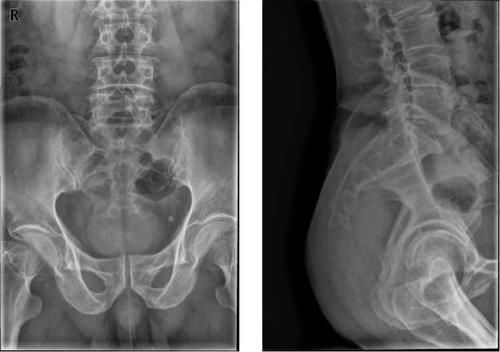

Case8:M,73y;右臀部疼痛伴右下肢放射痛2月。

文章插图